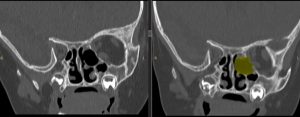

CT-ul efectuat imediat postoperator a confirmat ablația macroscopic completă (fig 2)

Figura 2: imagini CT comparative preop-postop la finalul interventiei chirurgicale